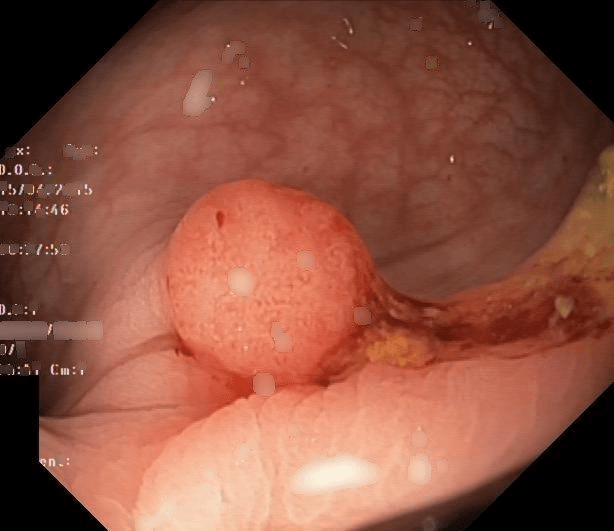

Refer to caption

(a) No abnormality

(b) Polyp

(c) Oesophagitis

(d) Ulcerative Colitis

Figure 1: Illustrations of question-answer pairs along with common abnormalities in gastrointestinal image from ImageCLEFmed-MEDVQA-GI-2023 dataset

The new dataset released for the ImageCLEFmed-MEDVQA-GI-2023 challenge is based on the HyperKvasir dataset [29], the largest gastrointestinal collections with more than 100,000 images, with the additional question-and-answer ground truth developed by medical collaborators. The development set and test set include a total of 3949 images from different procedures such as gastroscopy and colonoscopy, spanning the entire gastrointestinal tract, from mouth to anus. Each image has a total of 18 questions about abnormalities, surgical instruments, normal findings and other artefacts, with multiple answers possible for each, as shown in Table 1. Not all questions will be relevant to the provided image, and the VQA system should be able to handle cases where there is no correct answer. Figure 1 depicts several examples of question-answer pairs on common abnormalities in gastrointestinal tract, such as Colon Polyps, Oesophagitis, and Ulcerative Colitis. As shown in Figure 1(d), there are three possible answers to the question "What color is the abnormality?": "Pink," "Red," and "White", and a typical VQA system should be able to identify all three colors. In general, the image may contains a variety of noise and components that locates across abnormalities, such as highlight spots or instruments, which pose a significant challenge in developing efficient VQA systems for gastrointestinal domain.